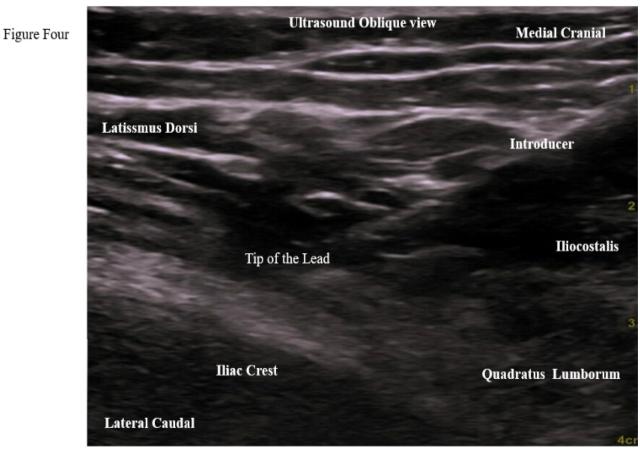

This case series aims to evaluate the effectiveness of the Micro Lead - SPRINT Peripheral Nerve Stimulation (PNS) System, (Cleveland, Ohio, USA) for treating cluneal neuralgia, utilizing both fluoroscopic and ultrasound guidance for accurate nerve localization.

A retrospective review was conducted on six nonconsecutive patients who underwent Micro Lead - SPRINT Peripheral Nerve Stimulation (PNS) System, (Cleveland, Ohio, USA) implantation for cluneal nerve entrapment at MetroHealth System between August 2021 and January 2024. Patient selection focused on individuals with cluneal neuralgia refractory to conservative treatments. Data collection included demographics, pain characteristics, opioid usage, and follow-up evaluations at 30, 60, 90 days, and 2 years post-procedure. Outcomes were assessed using the Numerical Rating Scale (NRS) for pain. Dividing the NRS score by the maximum score (10) and multiplying by 100 expresses pain intensity as a percentage.